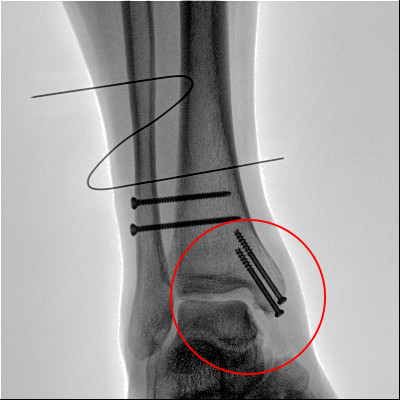

踝關節(jié)骨折在X影像上的表現(xiàn)有很多種。如內(nèi)踝骨折和外踝骨折,我們可以在影像上看到骨折處的骨折線是不連續(xù)的。還有后踝的骨折,內(nèi)踝、外踝、后踝聯(lián)合在一起發(fā)生的骨折,我們稱之為“三踝骨折”,這些都是在X影像上能夠顯示出來的。

外踝骨折